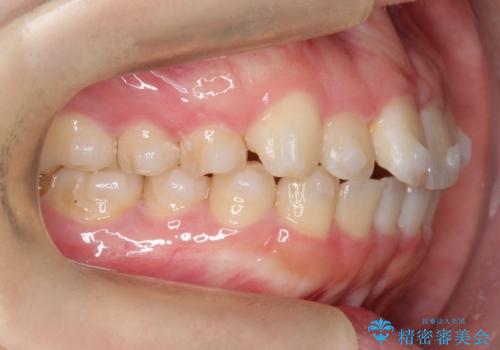

【インビザライン】前歯の凸凹をなおしたい

- 前歯のガタガタを主訴に来院されました。

インビザラインで綺麗な歯並びになり、患者さんには大変満足していただきました。

インビザラインは軽度叢生治療において優れた選択肢となります。